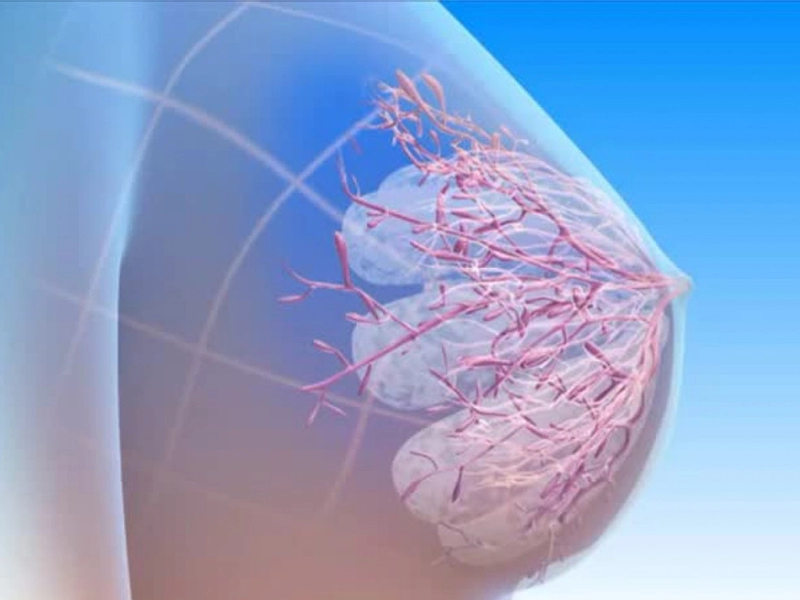

علائم سرطان سینه همیشه واضح نیستند و بسیاری از زنان بدون آنکه متوجه شوند، با نشانههایی زندگی میکنند که میتواند

جراحی سرطان سینه یکی از اساسیترین و موثرترین راهکارها برای کنترل و درمان این بیماری به شمار میرود. این جراحی